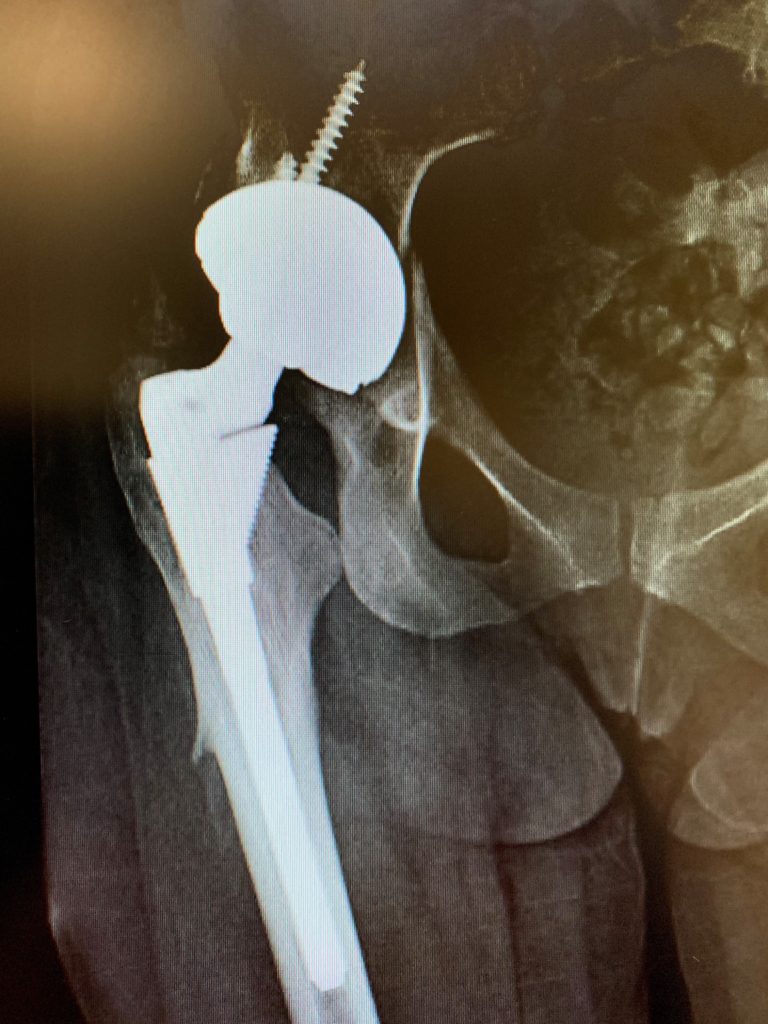

Ella es una no fumadora. Realizamos la cirugía de revisión a través de un abordaje lateral, el enfoque utilizado para su reemplazo inicial de cadera. Expusimos su cadera artificial por completo y solo eliminamos su componente acetabular.

Nuestro plan era cambiar este componente por una alternativa que facilitara una construcción de movilidad dual, una que haya demostrado abordar muy bien el problema de la inestabilidad.

Esto se hizo sin eventos y, en extensas pruebas de estabilidad, no se observaron dislocaciones. Después de la operación, Miss EM se sometió a una extensa fisioterapia para fortalecer sus abductores tanto como sea posible, otra estrategia para abordar su problema de inestabilidad. 1 año después de la operación, todavía se queja de rigidez en la cadera, pero no ha experimentado más dislocaciones.

Preoperatorio

Postoperatorio